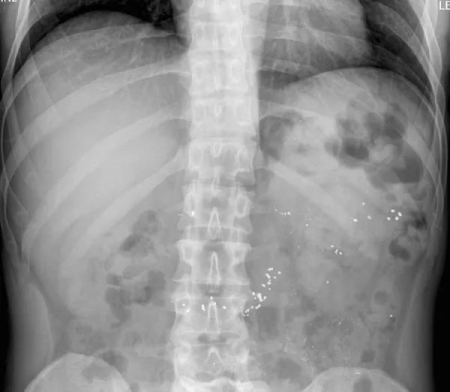

第二天,進行腹部X 光檢查以評估便秘情況,結果顯示結腸有均勻分佈的不透明斑點,直腸乙狀結腸區有適量大便和無梗阻性腸內氣體分佈,這種現象提示結腸有特別的物質,孩子的腹痛可能就跟它有關。

拿到這個X 光片,根據影像學特點,醫生的鑑別診斷方向從攝入不透射線的物質到慢性炎症都有,最常見的有鉛、汞、抗酸劑、鉍藥物等。

孩子結腸X 光顯示斑點的問題得到了解釋,基本排除了重金屬中毒以及嚴重腸道疾病的可能,他最終診斷為便秘。